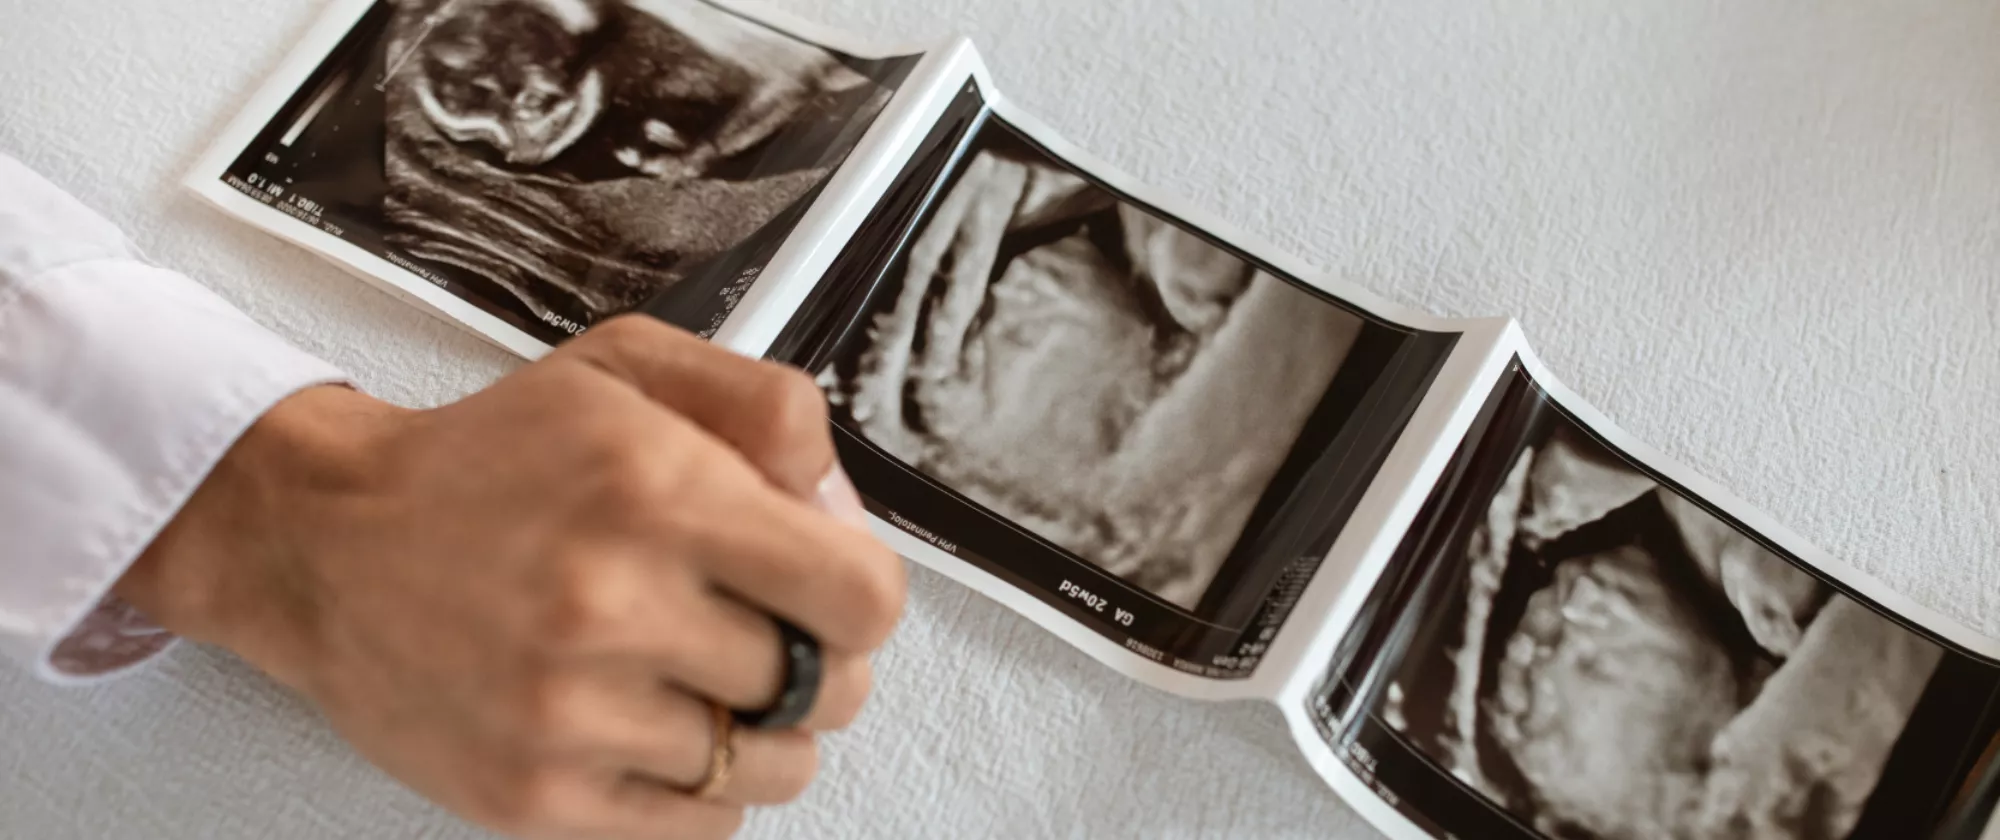

Trilogia 2026 – Overwiev sul primo trimestre in gravidanza

La Trilogia 2026 è un ciclo di tre formazioni dedicate al primo trimestre di gravidanza.

Questa serie di formazioni approfondisce il tema da prospettive diverse ed è rivolta specificamente ai professionisti del settore sanitario. Il focus è posto su approfondimenti pratici su aspetti diagnostici e clinici legati alla gravidanza precoce.

La seconda parte della trilogia si terrà giovedì 7 maggio 2026 ed è dedicata alla parte pratica

• Hands-on training in ecografia